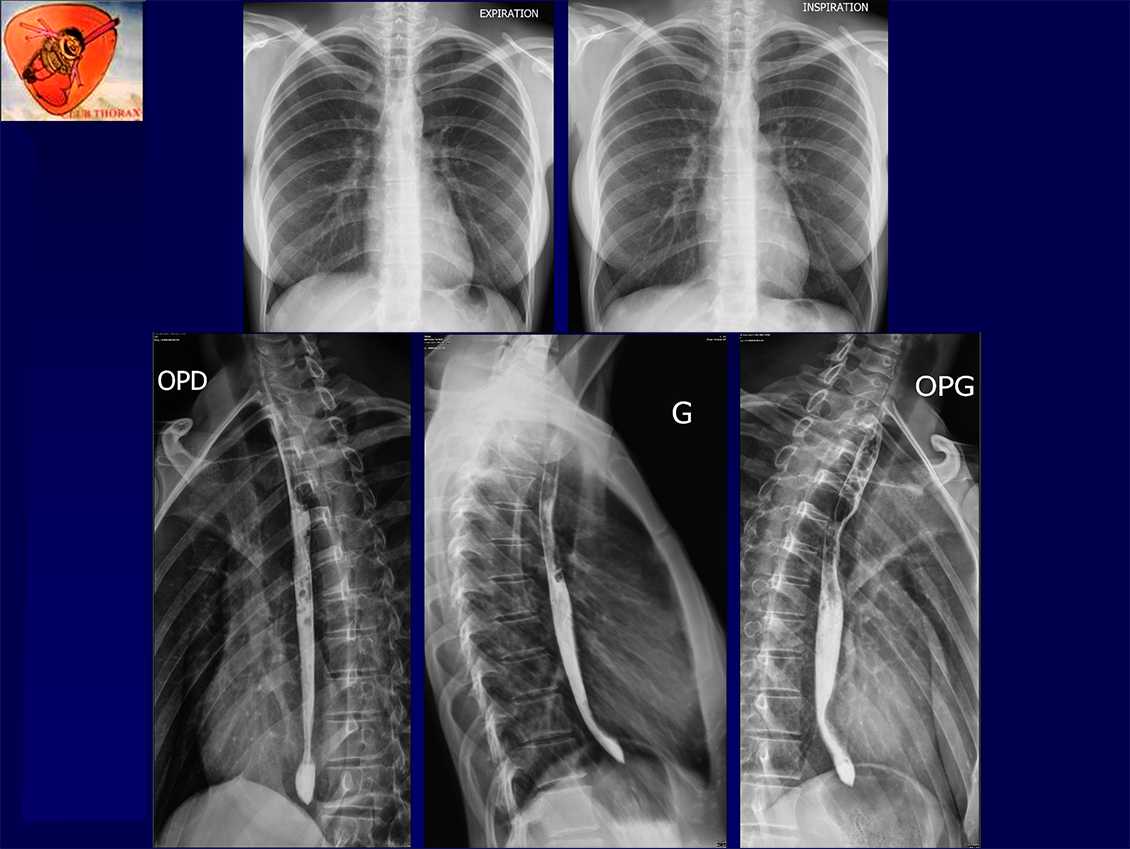

Femme 21ans, Douleur thorax brutale sans dyspnée.

Pas d’antécédent cardiothoracique particulier

Bon état général

Apyrétique

Auscultation: normale

Saturation à l’air ambiant: 98%

Pas de syndrome de MARFAN